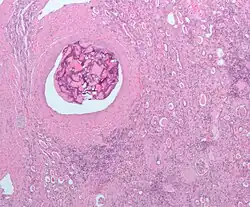

Peritoneum

Foreign bodies in the peritoneum can include retained surgical instruments after abdominal surgery. Rarely, an intrauterine device can perforate the uterine wall and enter the peritoneum.

Foreign bodies in the peritoneum eventually become contained in a foreign body granuloma. In the extremely rare case of retained ectopic pregnancy, this forms a lithopedion, which involves the fetus being too large to be reabsorbed, and is calcified[13] as a means of shielding the surrounding tissue from infection.